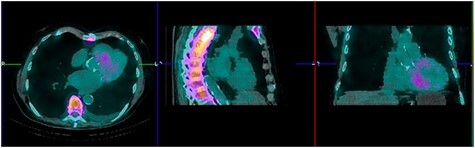

Tc-99 m pyrophosphate (PYP) single-photon-emission computed tomography demonstrated diffuse uptake of PYP throughout the left ventricle myocardium and increased uptake in the right ventricle free wall (Perugini Grade 3), consistent with ATTR-CA (Fig. 2). A clinical diagnosis was made and myocardial biopsy was not recommended. Bone marrow aspiration and biopsy (BMBA) was negative for multiple myeloma (MM). Left heart catheterization was nonrevealing and saliva genetic test for ATTR was negative for any mutation.

Figure 2 .

Perugini grade 3 uptake by myocardium consistent with TTR amyloidosis.